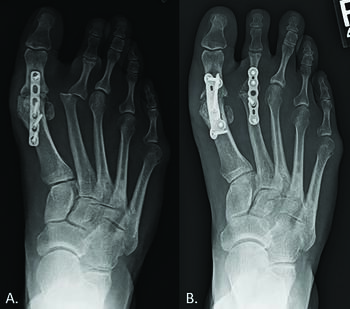

Implant Arthroplasty. Synthetic implants are a well-known treatment option to preserve motion in the first MPJ; however, there are limited reports of hemiarthroplasty or total MPJ replacement implants utilized in the lesser MPJ. Descriptions of replacement arthroplasty with silicone,11 ceramic,14 and titanium15 devices all exist. Implant arthroplasty provides patients with an option to decrease pain and retain motion at the MPJ; however, literature has not reported reliable success. Complications include prosthesis failure, loosening, synovitis, osteolysis, and increased potential for revision surgery.16 The senior author prefers a metatarsal head resurfacing implant as a primary “go-to” procedure for advanced arthritis of the second MPJ (see second photo set above). Our preferred implant system has a screw/post that lends immediate stability to the implant. Also, it does not require altering the weight-bearing surface of the metatarsal bone, which lessens the chance of developing postoperative transfer metatarsalgia.